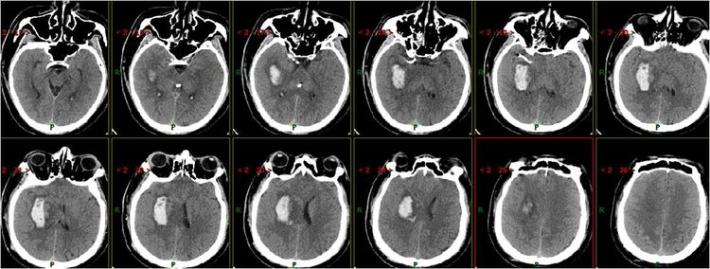

术后即刻复查头部CT

术中术后给予盐酸替罗非班应用12小时,桥接阿司匹林0.1g、氯吡格雷75mg,权衡利弊,未因核心梗死区出血转化停用抗血小板聚集药物。

患者术后1天,左侧肢体肌力0级,NIHSS评分:12分,复查头部CT:右侧基底节区出血,范围约22mmX49mm,请脑外科会诊:做好立体定向穿刺准备,注意观察患者病情变化,密集复查头部CT。

术后3天复查头部CT

术后7天复查头部CT

术后15天复查头部CT

术后21天复查头部CT